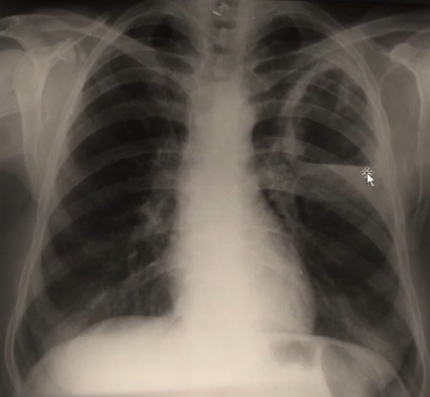

Rx toracică, incidență P-A

DESCRIERE: DAS + stază

indice cardiotoracic ↑

semne de dilatare a AS:

dublu contur inferior drept (contur dublu “festonat“)

deschiderea unghiului de bifurcație a traheei >120 grade

bombarea arcului mijl stg (golful pulm) → HTP

semne de stază pulm: dilatarea hilurilor + apicalizarea circulației + linii Kerley B

DX: stenoză mitrală

DD: insuf mitrală, boală mitrală, stenoză Ao